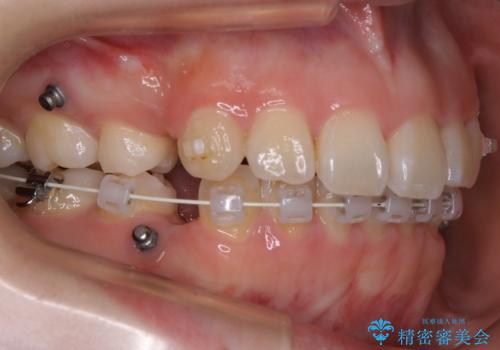

ハーフリンガル装置

ワイヤー矯正の中でも、上顎を裏側・下顎を表側に装置をつけて動かす方法をハーフリンガルといいます。

ハーフリンガルを選択すると、ワイヤー矯正の利点である抜歯ケースへの対応が可能な点と、表側の装置の欠点である装置が目立つという点をカバーして矯正治療を進めることができます。

表側の装置と違い、使えるワイヤーの種類に制限があり平均治療期間が長くなりやすい点、装置の作製自体の金額が掛かることから費用面で表側装置よりも高額になるという点はマイナスポイントであるといえますが、しっかりと口元を下げたり、噛み合わせの構築を行うことは遜色なく行えるため人気のある装置となっております。

また、裏側に装置が付くことによって喋り辛さを感じる方もいらっしゃいます。